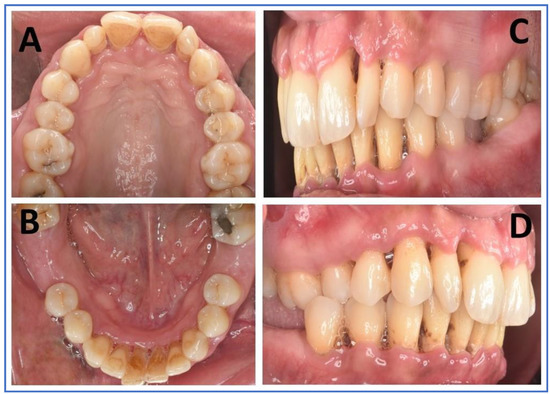

Extraoral examinations were within normal limits, focusing on facial symmetry, temporomandibular joint (TMJ), and potential trigger points of trigeminal neuralgia (TN). Upon intraoral examination, the patient had localized gingival inflammation in the upper and lower anterior areas, with punched-out papillae similar to necrotizing uncreative gingivitis (NUG). There was gingival recession of 2–7 mm, along with visible plaque and calculus in the same area and associated halitosis (Figure 3A–D). However, the pocket depth was not recorded due to severe pain upon touch, with a score of 9 out of 10 measured on the visual analog scale (VAS). Active dental caries at #16, 17 and previous restorations at teeth #24, 25, 37 were also observed (Figure 4).

Figure 3. Intraoral images (AD): (A) maxillary arch in palatal view with deposits in palatal aspect of anterior teeth, as well as composite restorations and dental caries in posteriors; (B) mandibular arch in lingual view showing deposits on the lingual aspect of anterior teeth, and the missing first molars of either side; (C,D) right and left lateral aspects showing deposits and gingival inflammation of marginal and interdental papillae, along with gingival recession.